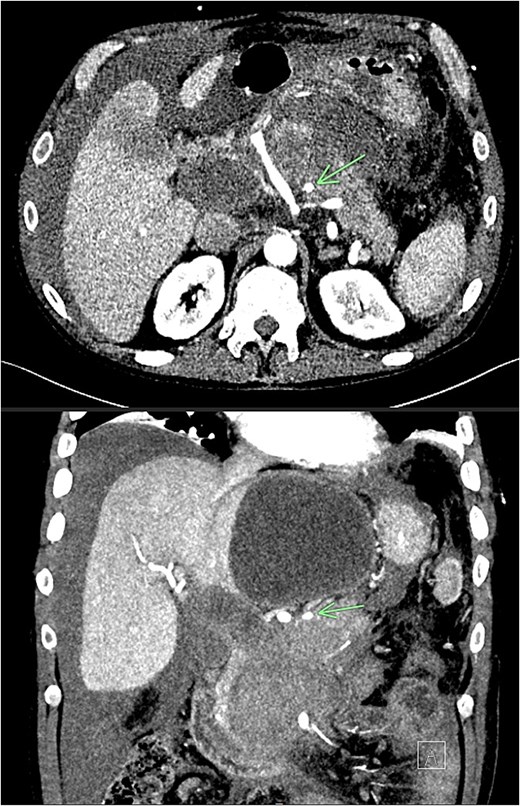

Recovery was complicated by progressive necrotising pancreatitis with evidence of active bleeding into a peripancreatic collection (Fig. 7) and a pseudoaneurysm arising from a branch of the superior mesenteric artery (SMA) associated with haemoperitoneum (Fig. 8).

CT angiogram of abdomen axial view; contrast extravasation, indicating active bleeding within this peripancreatic collection.

CT angiogram of abdomen axial and coronal view; small pseudoaneurysm arises from a branch of the SMA (arrow). Large haematoma in the head of the pancreas and diffuse haemoperitoneum throughout the abdomen/pelvis.